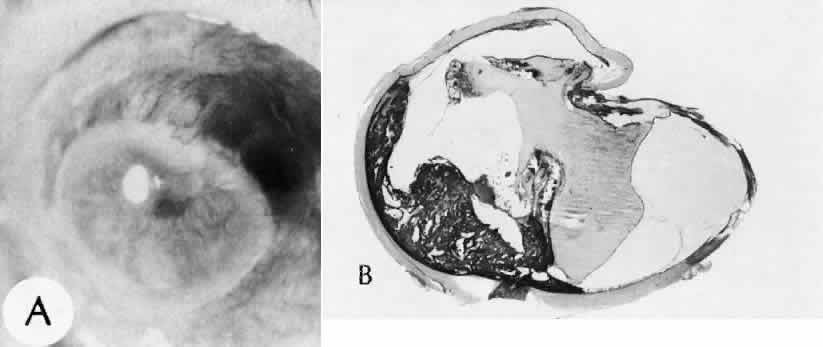

Expulsive choroidal hemorrhage (Fig. 30) is a rare catastrophic complication often resulting in total loss of the eye.93 The site of hemorrhage is probably a sclerotic choroidal arteriole where the vessel crosses the suprachoroidal space from the scleral canal. The sudden hypotension after surgical penetration of the globe causes a bending and then a rupture of the arteriole.94 Although most hemorrhages are massive and immediate, they occasionally are delayed, and some may not occur for days or weeks after surgery. Delayed choroidal hemorrhage may occur at the time of corneoscleral suture removal,95 because of clinically unapparent wound dehiscence or as a result of perforation of a corneal ulcer.

Fig. 30. A case of expulsive choroidal hemorrhage. A. Expulsive choroidal hemorrhage occurred 3 weeks after cataract surgery at the time when a limbal suture was removed. The intraocular pressure was reduced enough to allow shearing forces in the superficial choroid to tear an arteriole resulting in a high-pressure hemorrhage. B. In another case enucleated shortly after cataract extraction because of expulsive hemorrhage, accumulated blood can be identified in the suprachoroidal space. Because of the loose attachment of the choroid to the sclera, all intraocular contents were displaced toward the cataract wound. (Hematoxylin-eosin stain; × 3.)

Histologically, massive choroidal hemorrhagic detachment is associated with a retinal detachment. The retina and choroid may herniate through the scleral wound. A ruptured ciliary artery may be found in the suprachoroidal space.